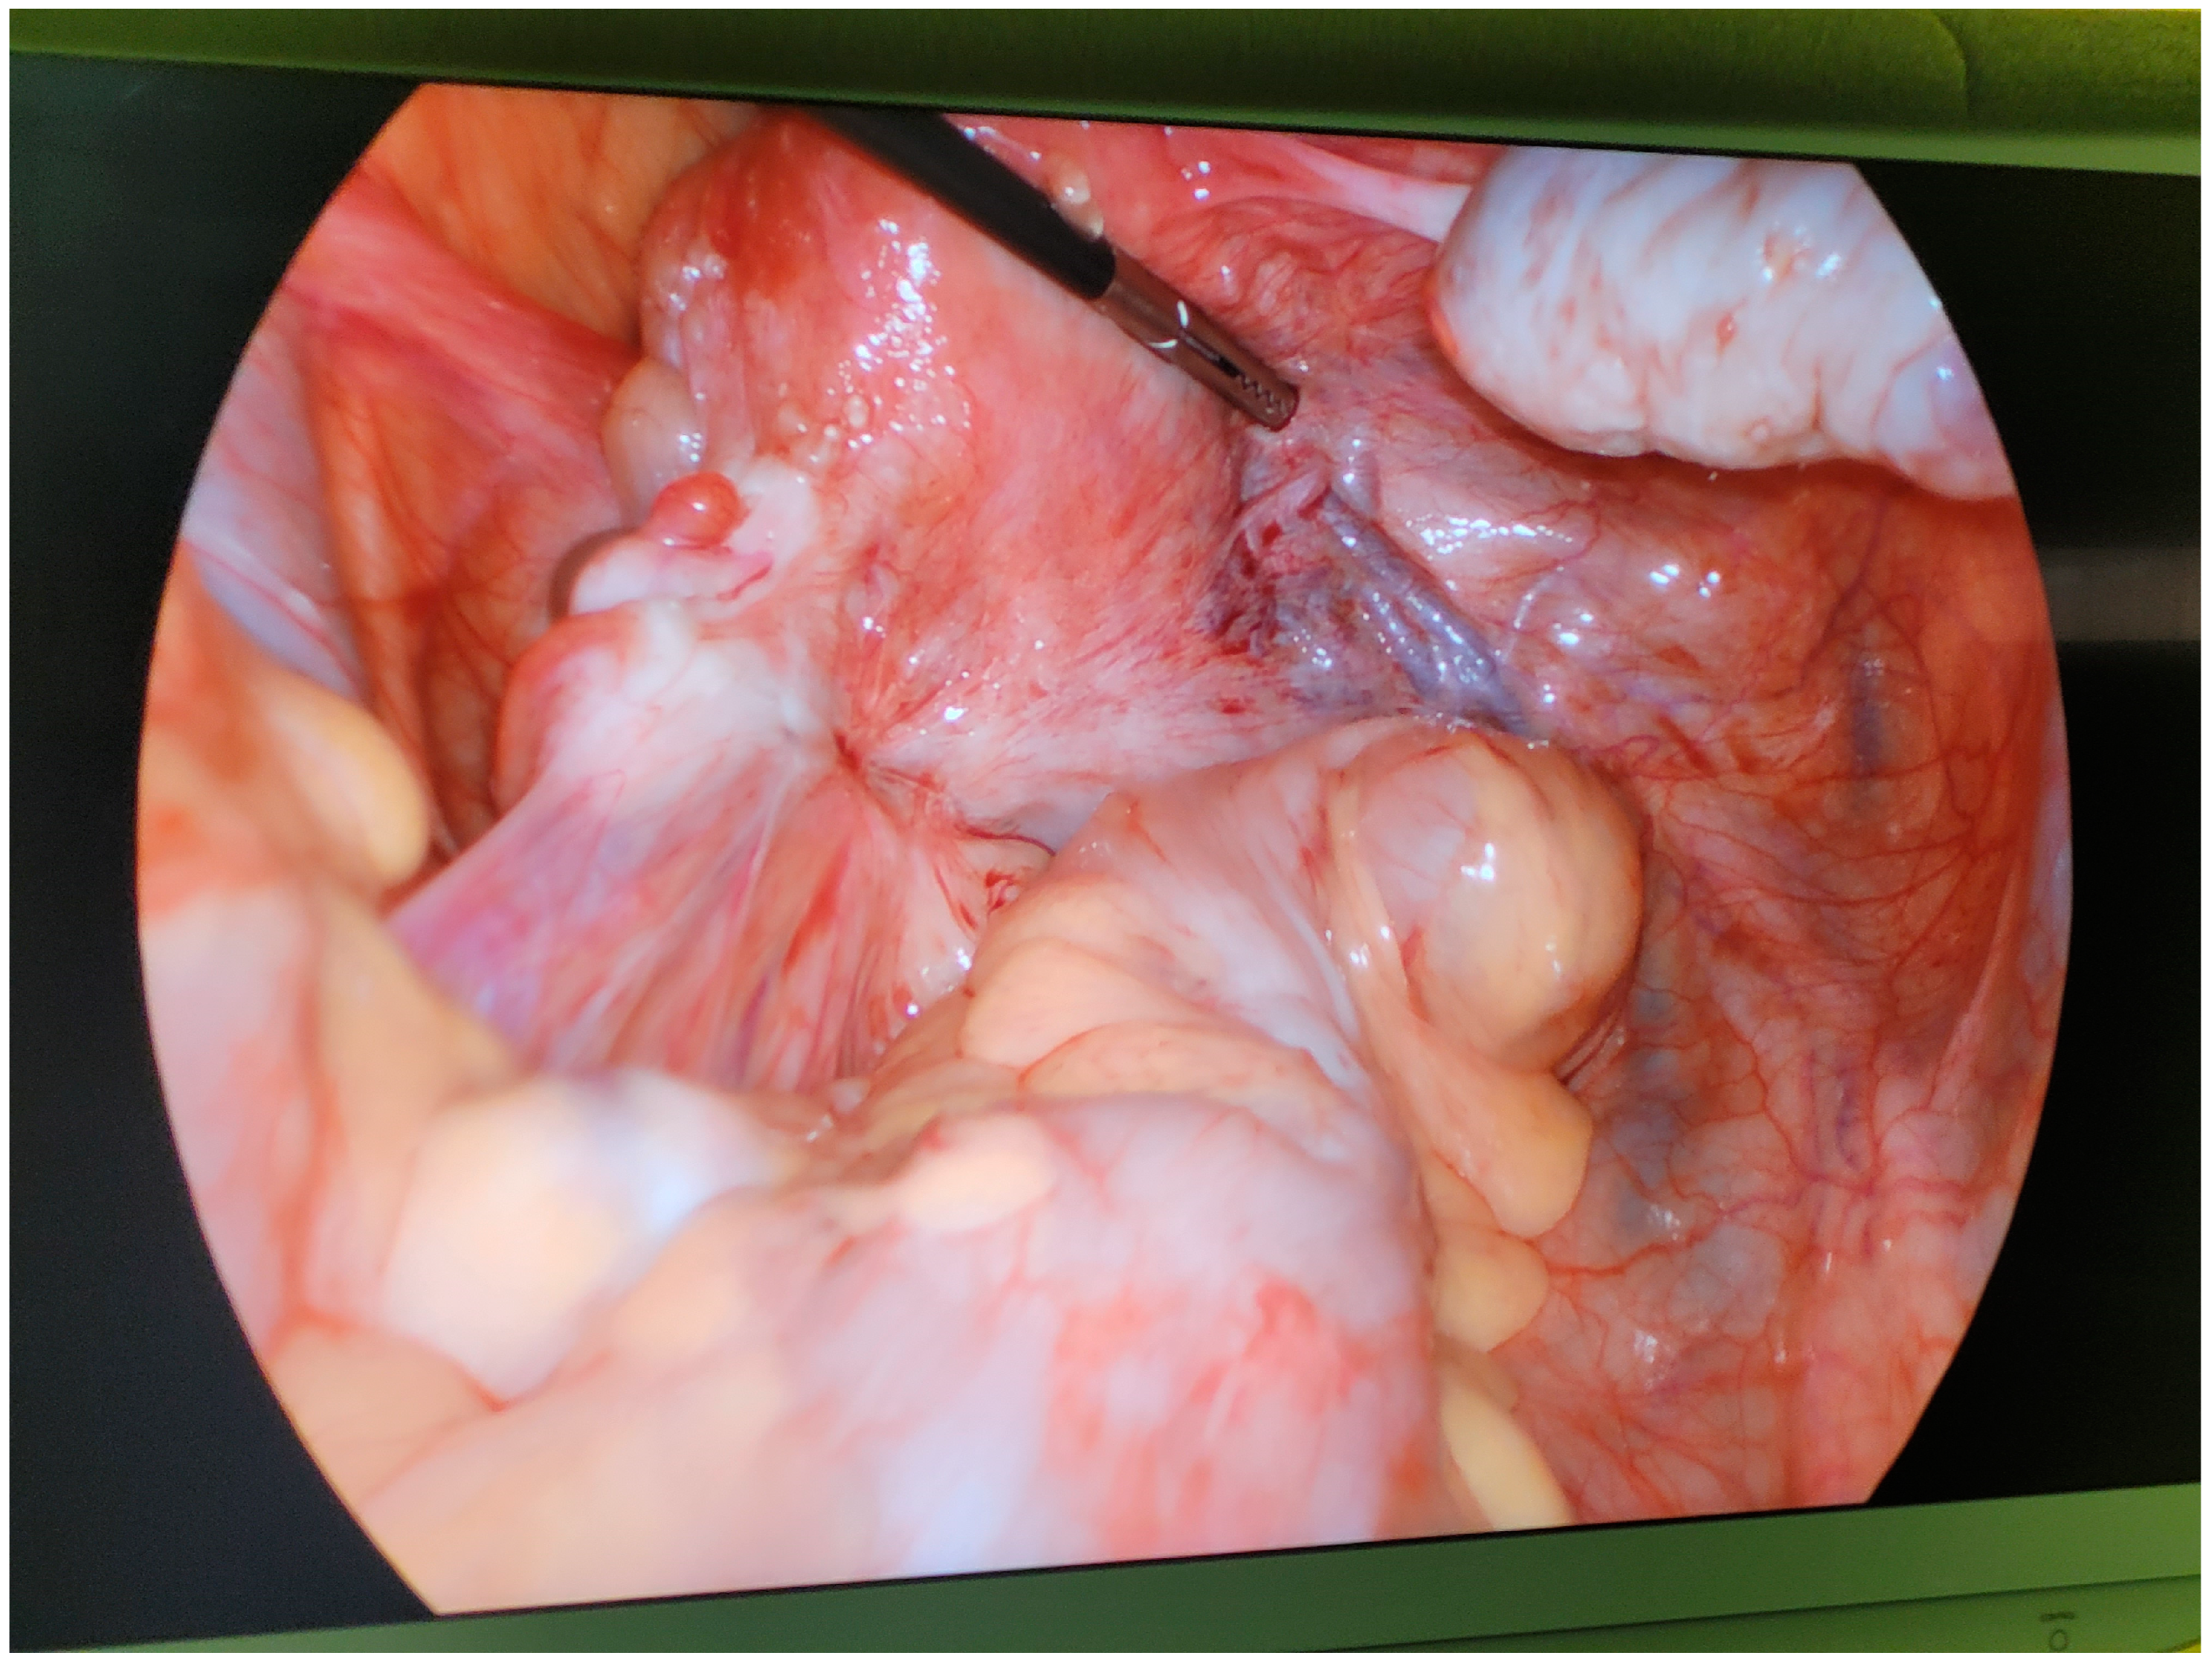

During the laparoscopic stage of the procedure, old postoperative adhesions in the area of the left ovary were found (Figure 2) and removed. Deep infiltrating endometriosis with associated fibrosis of the left ovarian fossa was confirmed, with the ureter trapped in a thick adhesion between the posterior uterine wall and sigmoid colon. The ureter was released, and the accompanying endometriosis was dissected by means of evaporation and cold resection to a degree that the ureter could regain its appropriate lumen. The walls of the left ureter and all adjacent blood vessels, particularly the left uterine artery, remained uninjured.

Figure 2.

Endometriotic adhesions and fibrosis involving the left ovary and tube, sigmoid colon, and peritoneum found at laparoscopy (27 March 2022).